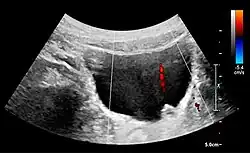

Cystic renal masses

Masses are seen as a distortion of the normal renal architecture. Most renal masses are simple cortical renal cysts with a round appearance and a smooth thin capsule encompassing anechoic fluid. The incidence increases with age, as at least 50% of people above the age of 50 have a simple cyst in one of the kidneys. Cysts cause posterior enhancement as a consequence of reduced attenuation of the ultrasound within the cyst fluid (Figure 5). The simple cyst is a benign lesion, which does not require further evaluation.[1]

Complex cysts can have membranes dividing the fluid-filled center with internal echoes, calcifications or irregular thickened walls. The complex cyst can be further evaluated with Doppler US, and for Bosniak classification and follow-up of complex cysts, either contrast-enhanced ultrasound (CEUS) or contrast CT is used (Figure 6). The Bosniak classification is divided into four groups going from I, corresponding to a simple cyst, to IV, corresponding to a cyst with solid parts and an 85–100% risk of malignancy.[1] In polycystic kidney disease, multiple cysts of varying size in close contact with each other are seen filling virtually the entire renal region. In advanced stages of this disease, the kidneys are enlarged with a lack of corticomedullary differentiation (Figure 7).[1]

Figure 5. Simple renal cyst with posterior enhancement in an adult kidney. Measurement of kidney length on the US image is illustrated by '+' and a dashed line.[1] -

Figure 6. Complex cyst with thickened walls and membranes in the lower pole of an adult kidney. Measurements of kidney length and the complex cyst on the US image are illustrated by '+' and dashed lines.[1] -